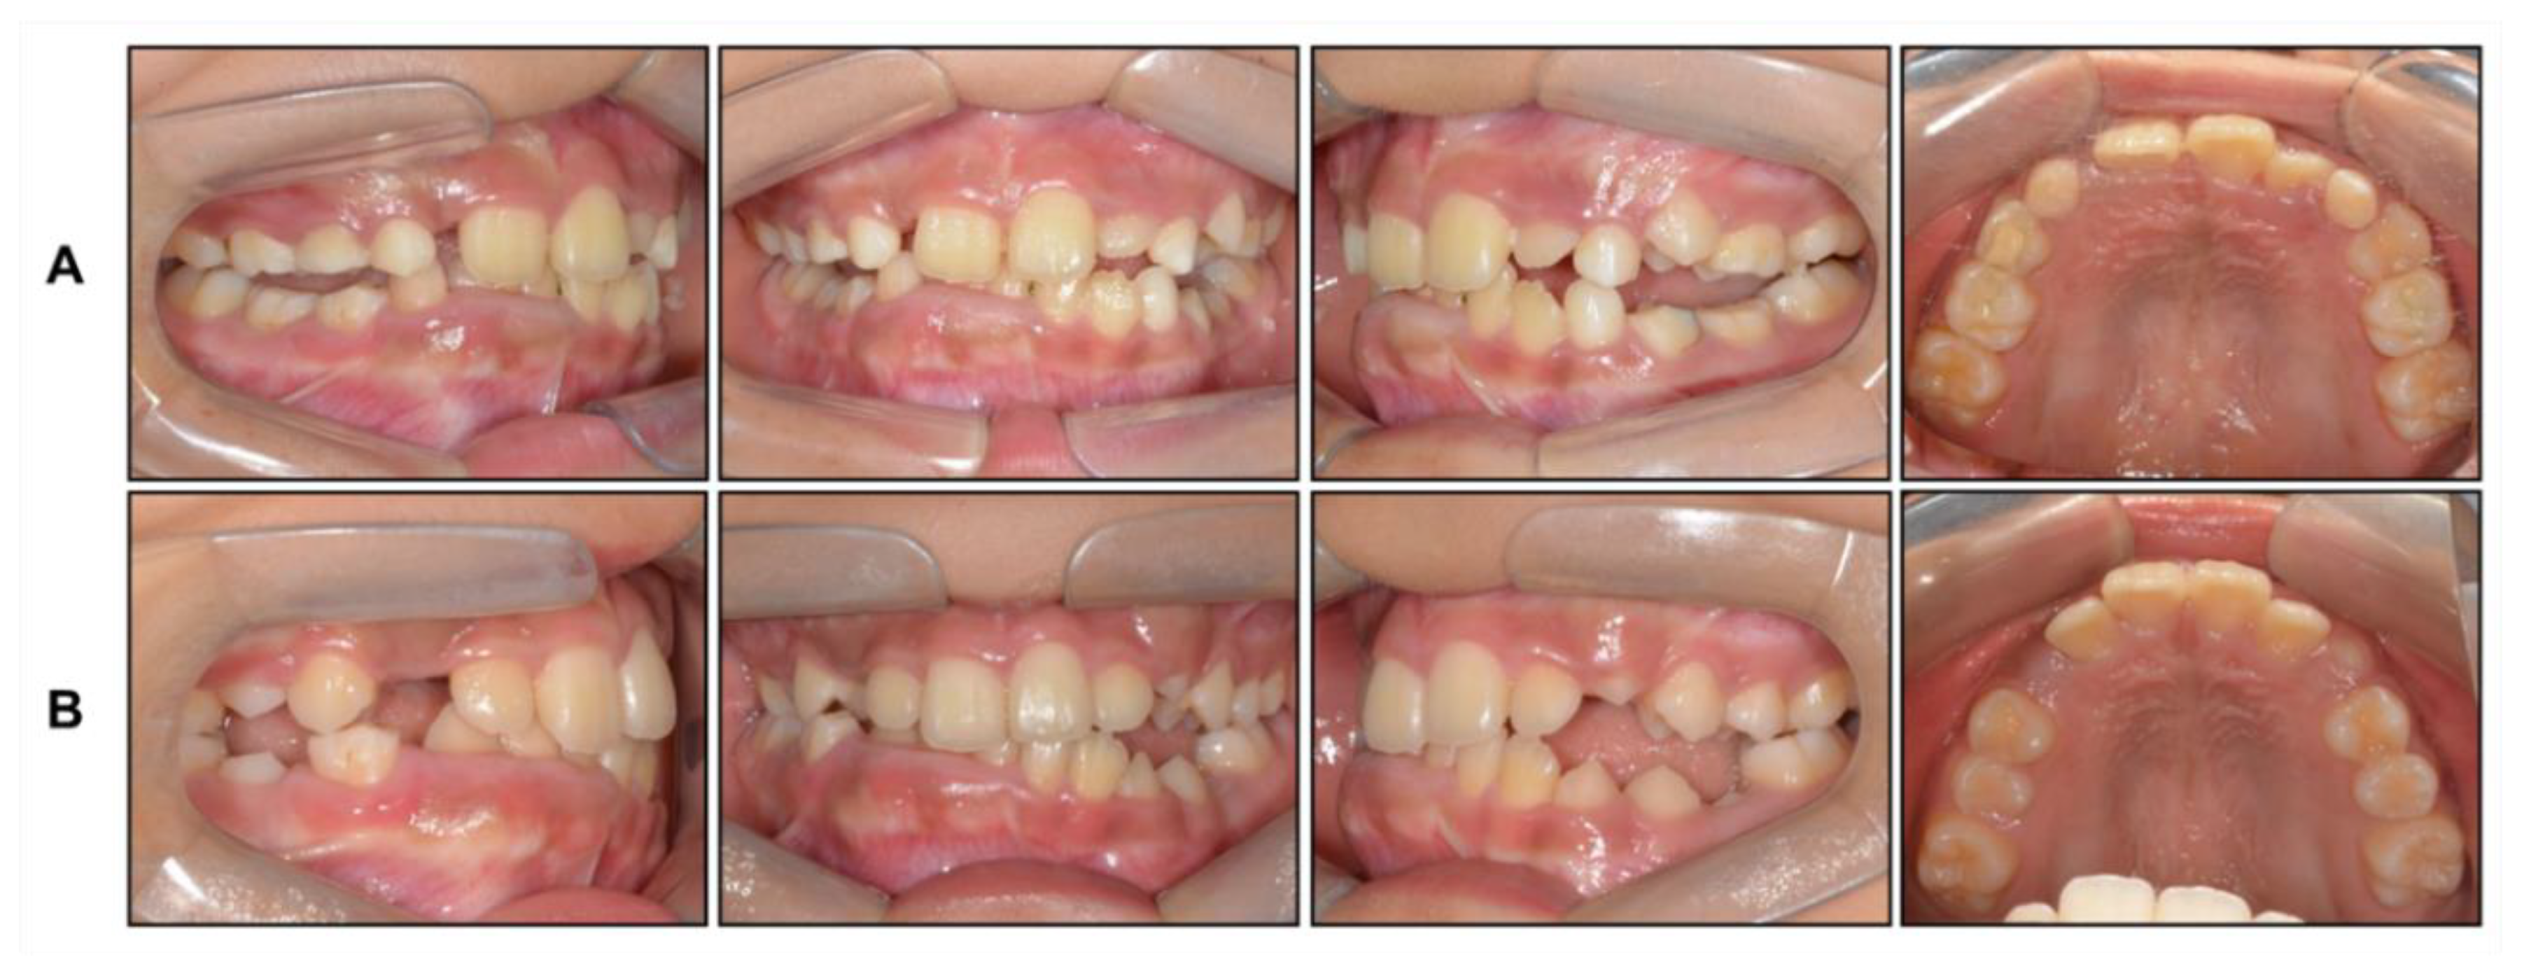

Figure 4. Intraoral photographs: (A) After face mask treatment; (B) At the end of phase 1 treatment.

Based on this, we decided to start an orthopedic treatment and closely follow up the hypertrophic region. We placed a bonded rapid palatal expansion appliance with a hook for the face mask, and the screw was turned once a day for 2 weeks. The separation of the midpalatal suture was confirmed, and the face mask was set up with the instruction of wearing it for at least 14 h a day. After 5 months, the crossbite was relieved, and the anteroposterior jaw relationship was improved. Nevertheless, there was still a lack of space for the eruption of permanent teeth on the maxillary dentition (Figure 4A). We stopped the use of the face mask and set up an active removable appliance on the maxilla to gain space. After 18 months, sufficient space was made on the maxillary dentition, and we decided to finish the phase 1 treatment (Figure 4B and Figure 5).